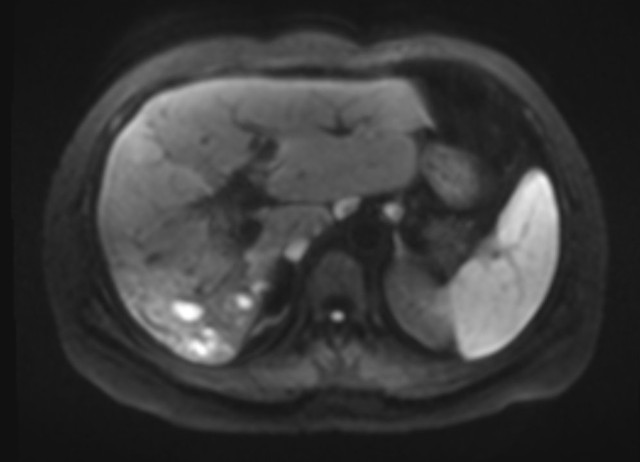

Axial diffusion weighted imaging: mass and filling defects demonstrate hyperintense signal on high B value diffusion imaging •MRCP and axial T2 fat saturation: diffuse intrahepatic biliary duct dilation; axial T2 fat saturation images confirm HASTE findings.

•Axial and coronal T2WI (HASTE sequences): An ~9cm hepatic mass with heterogenous, but predominately hyperintense signal, on T2WI. Associated intrahepatic biliary duct dilation with multiple curvilinear hypointense striations/filling defects.

•Pre and post-contrast T1 fat saturation images: predominately T1 hypointense mass with areas of intrinsic enhancement. Answer: Intraductal papillary neoplasm of the bile duct (IPNB)